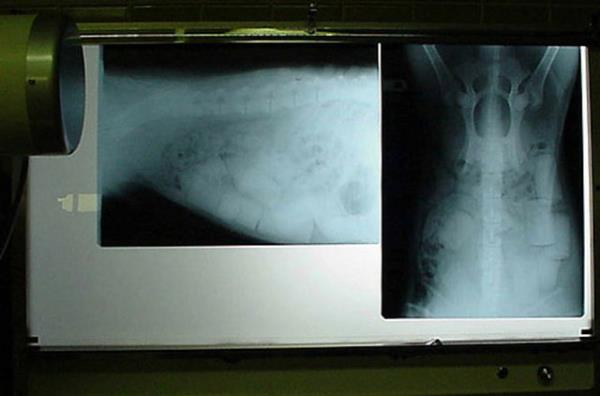

24. Avusturalya'da yaşayan bu sevimli Koalo'ya araba çarptı ama kurtuldu. Melbourne Hayvan Merkezi'ne götürülen Koalo'nun çekilen röntgen filminde kolunun kırıldığı farkedildi.

Avusturalya'da yaşayan bu sevimli Koalo'ya araba çarptı ama kurtuldu. Melbourne Hayvan Merkezi'ne götürülen Koalo'nun çekilen röntgen filminde kolunun kırıldığı farkedildi.